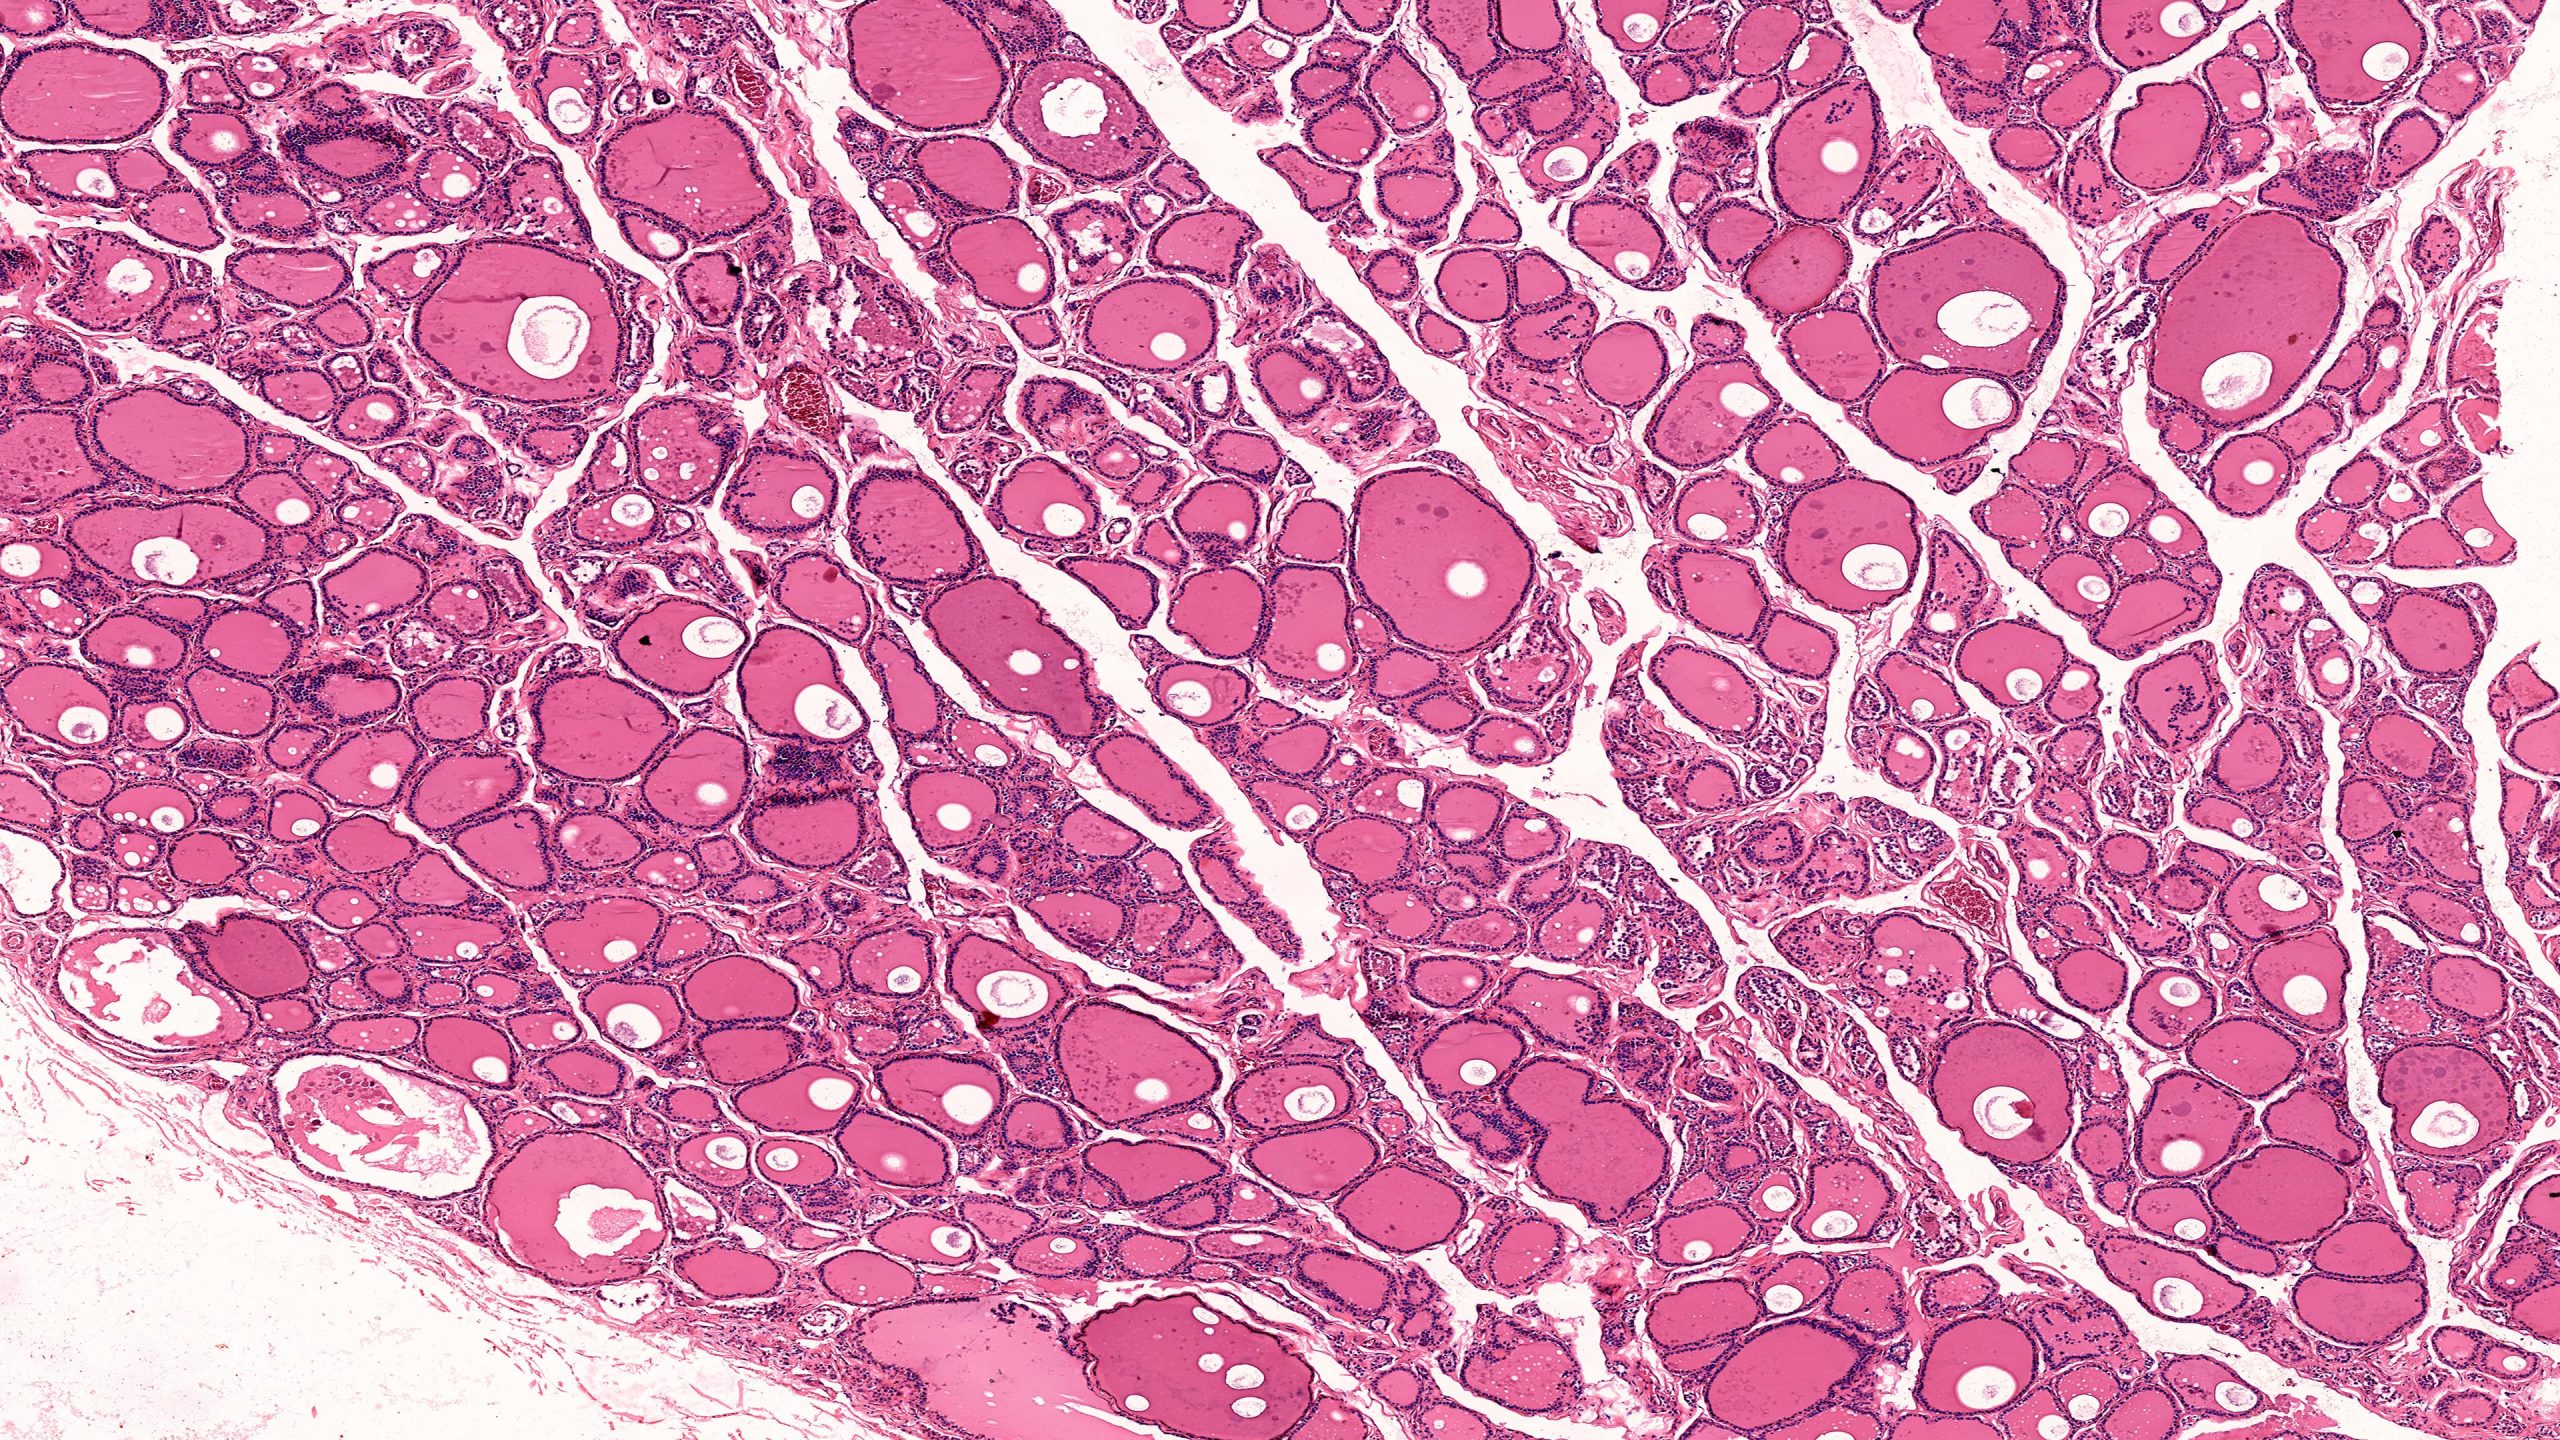

Thyroid and Parathyroid 40X